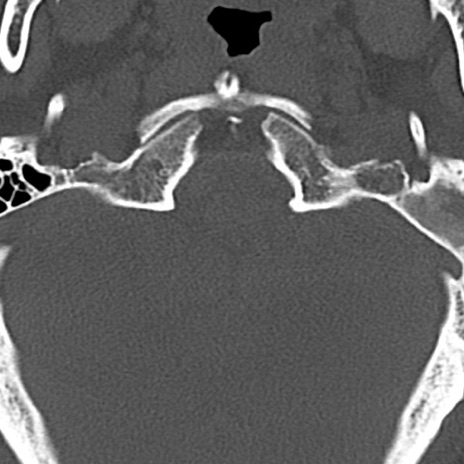

頚椎CT

横断像